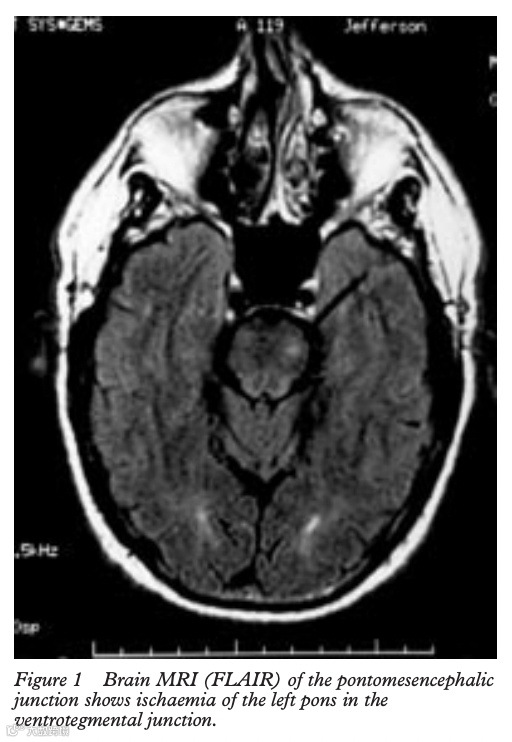

不过也有因为大脑出现罕见疾病,比如脑桥和延髓的梗塞,可能导致情感不稳定,进而无法控制大笑的情绪,结局有可能是晕厥,也有可能是死亡。

2001年一篇发表在《神经外科精神病学杂志》记载了一则罕见病例,一名65岁的男子出现了无法控制的大笑,随后短暂的右臂麻痹,同时右半边面部神经麻痹,偶尔哭泣。磁共振血管造影(MRA)和血管造影显示左脑桥和小脑小面积梗死、左椎动脉闭塞、右椎动脉和基底动脉狭窄。之后,他的病情恶化为双侧脑干梗塞,最终死亡。